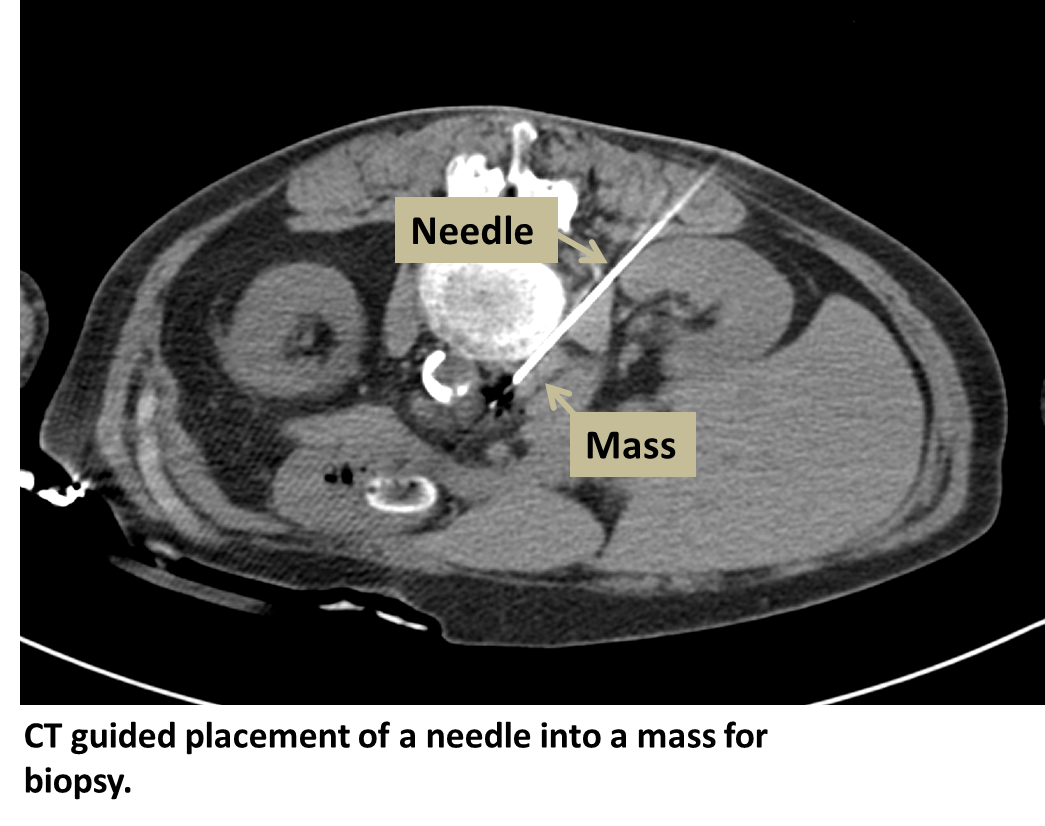

What Is Interventional Radiology Biopsy . An interventional radiologist or chest radiologist uses ct to guide a narrow gauge introducer needle into the lesion. A biopsy needle is then passed. An organ biopsy is a procedure in which your interventional radiologist uses a special needle to obtain a tissue sample for examination under a. An interventional radiologist uses ct or ultrasound to pass an introducer needle into the tissue of interest. Once position is confirmed, a biopsy.